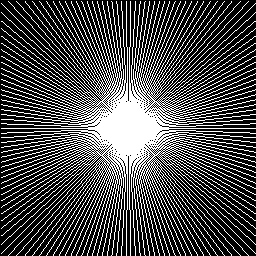

Refer to caption

(a) 10%

(b) 20%

(c) 30%

(d) 40%

Figure 7: Radial sampling masks used in our experiments.

We used two sets of MR images from the IXI database444\urlhttp://brain-development.org/ixi-dataset/ (the brain dataset) and from the Data Science Bowl challenge 555\urlhttps://www.kaggle.com/c/second-annual-data-science-bowl/data (the chest dataset) to assess the performance of our method by comparing our results with state-of-the-art CS-MRI methods (e.g., Convolutional sparse coding-based [20, 21], patch-based dictionary [19, 37, 18], deep learning-based [26, 24, 25, 27], and GAN-based [33, 32]). The image resolution of each image is 256x256. From each database, we randomly selected 100 images for training the network and another 100 images for testing (validating) the result. We conducted the experiments for various sampling rates (i.e., 10%, 20%, 30%, and 40% of the original k𝑘k-space data), corresponding to 10×\times, 5×\times, 3.3×\times, and 2.5×\times factors of acceleration. We assume the target MRI data type is static, and radial sampling masks are applied (Figure 7). It is worth noting that our experimental data are real-valued MRI images, which require pre-processing of the actual acquisition from the MRI scanner because the actual MRI data is complex-valued. Additional data preparation steps, such as data range normalization and imaginary channel concatenation, are also required.